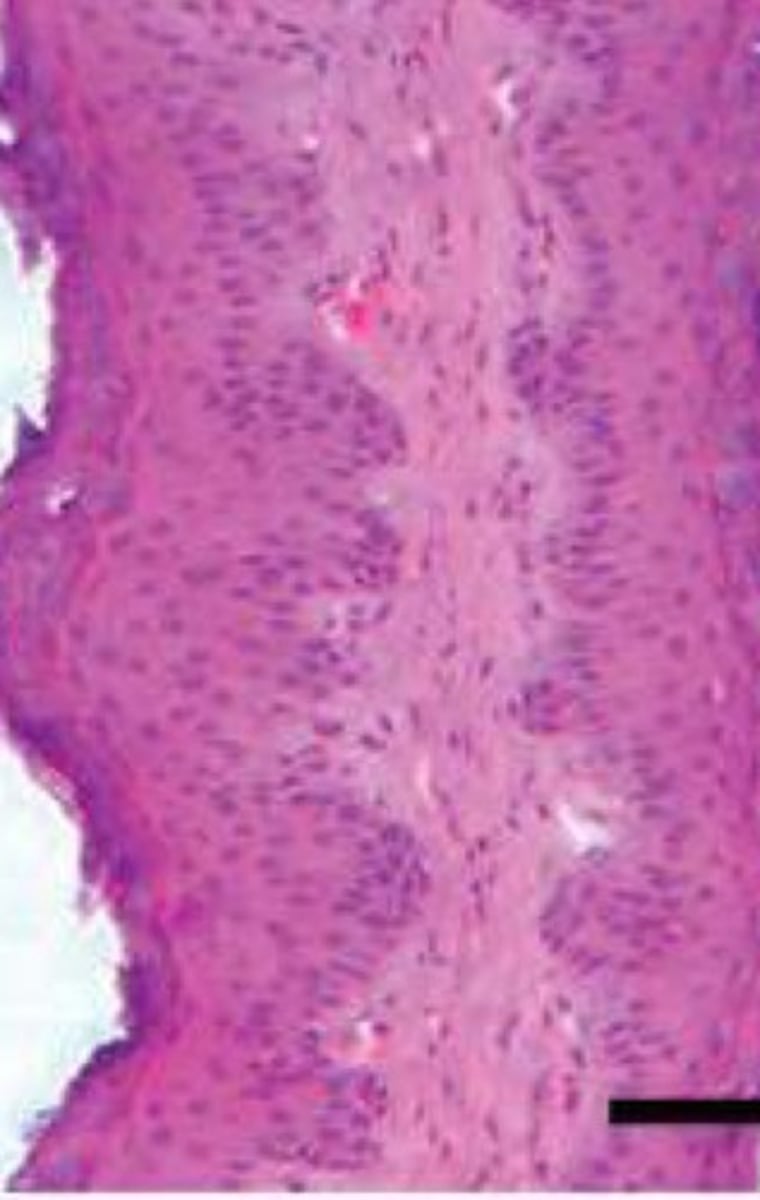

What is the transition period of the rumen epithelium during pregnancy?

3 weeks before calving to 3 weeks after

At 3 weeks prior to calving, the rumen epithelium will appear ______, and overfeeding can lead to _______

Thick, dystocia

One week after calving, the rumen epithelium will appear thinner in response to an increase in ______ _____

Milk production

3 weeks after calving, the rumen epithelium will be at its _______ and most efficient due to high energy demands

Thinnest